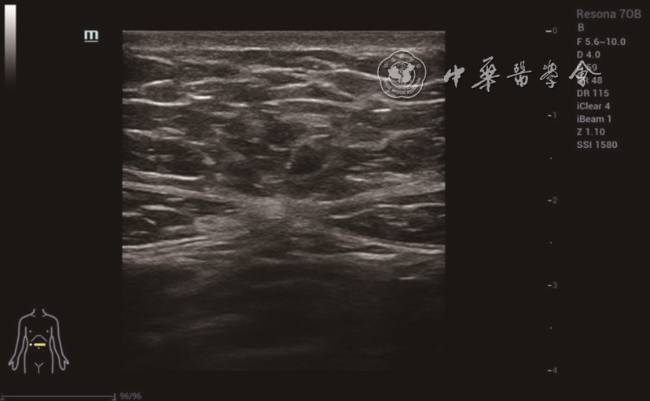

2. 方法:受检者平躺,暴露腹部检查区域,采用横向、纵向、斜向多平面结合方式先进行实时二维灰阶扫查,观察剑突以下至耻骨联合以上的腹直肌情况,测量脐水平、脐上5 cm水平、脐下5 cm水平的双侧腹直肌高回声筋膜内侧缘间的距离,记录为IRD0、IRD+5、IRD-5图12)。二维超声定位双侧腹直肌内侧1~2 cm范围内的部位,嘱患者屏气3~5 s,开启SWE扫查模式,剪切波弹性的量程为0~180 kPa,待图像稳定后冻结,选择感兴趣区域(region of interest,ROI),ROI范围为双侧腹直肌内侧1~2 cm的最大测量面积(不包括腹直肌筋膜),手持探头在检测部位,不施加压力。双幅实时显示功能观察二维图与弹性图,选取ROI,静置3~5 s,保持探头稳定以获得稳定弹性图(M-STB Index:5颗绿星)并保存,观察和记录该区域弹性模量颜色分布特征。仪器自带Q-BOXTM定量测量工具,测量ROI范围内杨氏弹性模量值[平均值(Emean)、最大值(Emax)、最小值(Emin)],每个区域(右侧腹直肌脐水平R0、左侧腹直肌脐水平L0、右侧腹直肌脐上5 cm水平R+5、左侧腹直肌脐上5 cm水平L+5、右侧腹直肌脐下5 cm水平R-5、左侧腹直肌脐下5 cm水平L-5)中部水平测量2次,取平均值(图34)。

图1 22岁未育女性,脐上5 cm水平双侧腹直肌间距为0 cm

图2 35岁初产妇产后43 d,脐上5 cm水平双侧腹直肌间距为2.3 cm